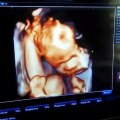

USG 3/4D LUBLIN USG 3D 4D LUBLIN - 1

PRACOWNIA USG 3D 4D 3/4D <br />CENTRUM MEDYCZNE PROVIVO <br />LUBLIN, Jutrzenki 10/6A <br />www.provivo.com.pl <br />tel. 607 287 912